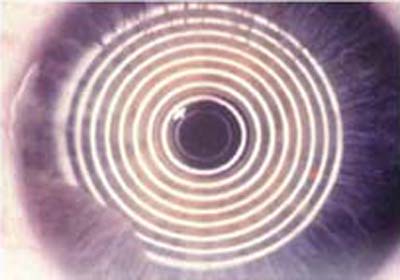

Con la difusión de la cirugía refractiva a finales de los años 70 y comienzos de los 80, fué necesario mejorar la metodología clínica existente para medir la superficie anterior de la córnea. Basados en el Queratómetro, se desarrollaron los Fotoqueratoscopios para poder capturar la imágen de los anillos del Disco de Placido reflejados sobre la córnea,pudiendo así, apreciar en forma cualitativa, distorsiones inherentes a una forma de córnea individual; ( foto N° 1)